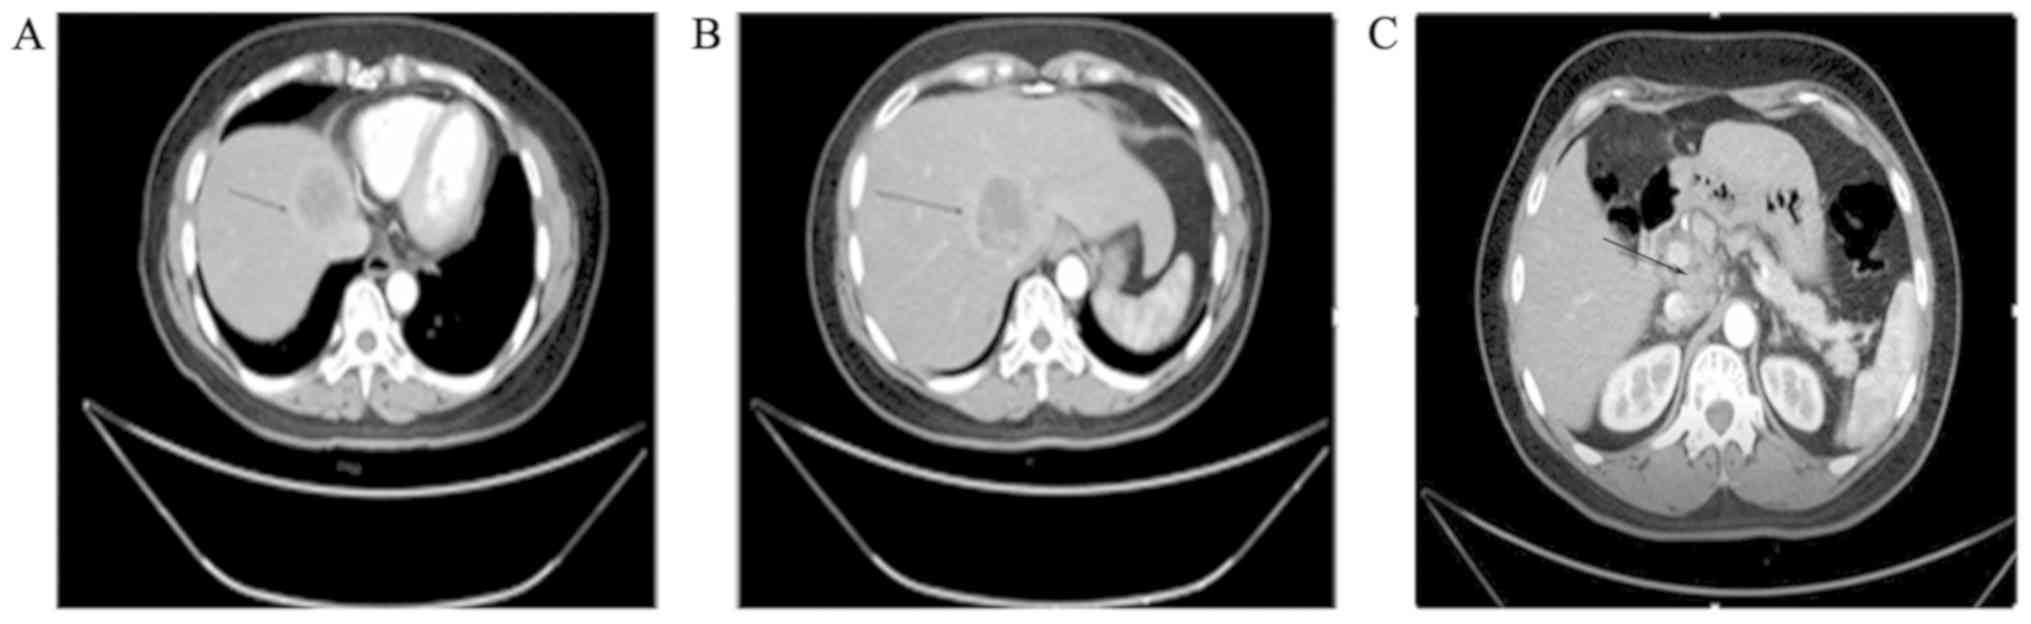

A 55-year-old woman presented with chest and back pain of unknown etiology. The patient was admitted to the West China Hospital (Chengdu, China) for further examination and treatment. Laboratory data revealed increased levels of α-fetoprotein (AFP), serum carbohydrate antigen (CA)125 and NSE, which were 23.41 ng/ml (normal range <20 ng/ml), 62.26 U/ml and 127.9 ng/ml, respectively. The AFP values associated with primary hepatocellular carcinoma are generally known to be >500 ng/ml for 4 weeks, or 200-500 ng/ml for 8 weeks. Therefore, the diagnosis of primary liver cancer in this patient was not considered likely. CA125 is widely present in mesothelial tissue and is currently the most important ovarian cancer-associated antigen. CA125 is the most reliable diagnostic indicator for ovarian cancer, and its normal level is <35 U/ml, whereas NSE is mainly used for the diagnosis of neuroendocrine tumors, with a serum reference value of <12.5 ng/ml. Contrast-enhanced computed tomography (CT) examination revealed low-density tumors sized 4.6 and 4.4 cm in the caudate and left internal lobe of the liver, respectively (Fig. 1A and B). There were multiple enlarged lymph nodes along the abdominal aorta, the hepatogastric and gastrosplenic ligaments, and in the space between the portal vein and the inferior vena cava (Fig. 1C). The patient was subjected to left three hepatic resection (including left inner lobe, left outer lobe and right anterior lobe resection), abdominal lymph node dissection, liver tumor radiofrequency ablation, hepatic caudate lobe resection, intestinal adhesion release, repair of vena cava damage, portal vein repair and hilar cholangioplasty in our hospital. The liver margin of the surgical specimen was not invaded by cancer. Subsequent immunohistochemical examination did not rule out the possibility of a gastrointestinal origin, and gastrointestinal endoscopy and positron emission tomography (PET)-CT were performed to exclude distant metastasis. Upper gastrointestinal endoscopy revealed chronic non-atrophic gastritis and esophagitis (grade B). Endoscopic examination of the lower digestive tract detected polyps of the colon, diagnosed as tubular adenomas following biopsy and histopathological examination. The PET examination demonstrated active glucose metabolism in the liver, cervical lymph nodes, abdominal lymph nodes and bones, mostly due to tumor metastases (Fig. 2). There was no evidence of intestinal, ovarian or other metastases.

Figure 2.

Positron emission tomography examination revealed increased glucose metabolism in (A) the neck lymph nodes, (B) abdominal lymph nodes and (C) the residual liver, whereas (D) multiple bone metastatic lesions were also detected.